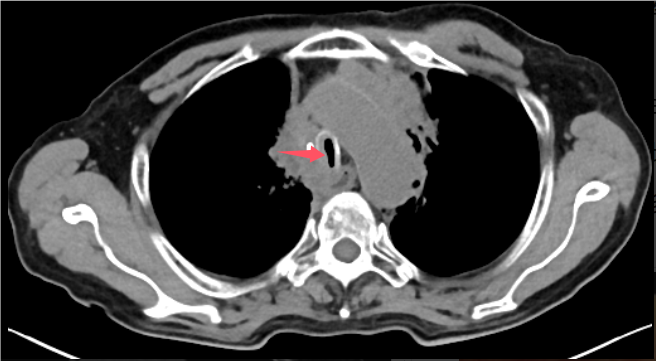

術前胸部CT見患者氣道狹窄,呈一縫隙